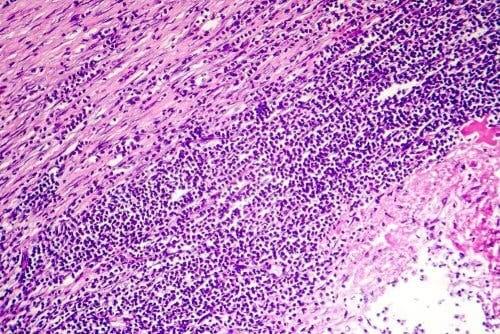

Det er umulig å fastslå årsaken til perikarditt i omtrent 80 % av tilfellene. Det er imidlertid veldig vanlig at opprinnelsen er et resultat av en slags infeksjon. Det er veldig sannsynlig at det er en virusinfeksjon. Det kan være en bakteriell infeksjon, men i mindre grad, og bare veldig sjelden kan det skyldes en soppinfeksjon.